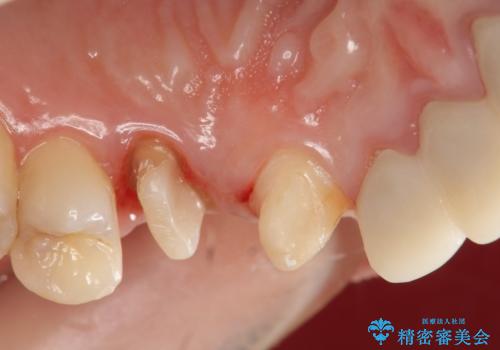

左上4の補綴物を除去したところ縁下歯質だったため、歯牙の挺出を提案し行いました。

挺出終了後は歯肉切除および骨外科により歯周組織を整え、オールセラミッククラウンによる補綴を行いました。

縁下カリエス(歯茎より深い虫歯)の治療について

虫歯が進み歯茎より深くなってしまうと、虫歯を取り残してしまうリスク、樹脂の硬化の妨げ、補綴物の不適合、歯肉炎・歯周病のリスクの増大等様々な弊害が起こり得ます。

そのため当院では歯周外科手術(歯茎を下げる手術)や歯の挺出による、虫歯が歯茎より深いという問題の解決を推奨しております。